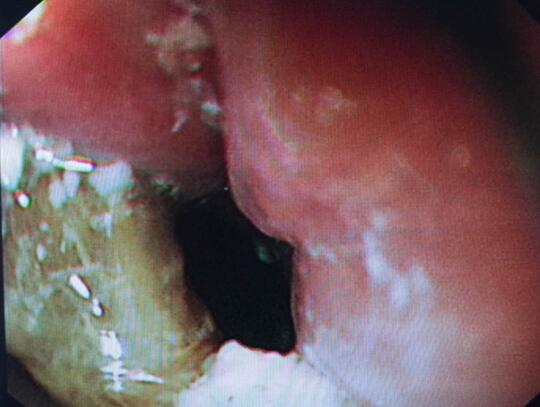

钛夹逐渐夹闭损伤

钛夹完全夹闭损伤